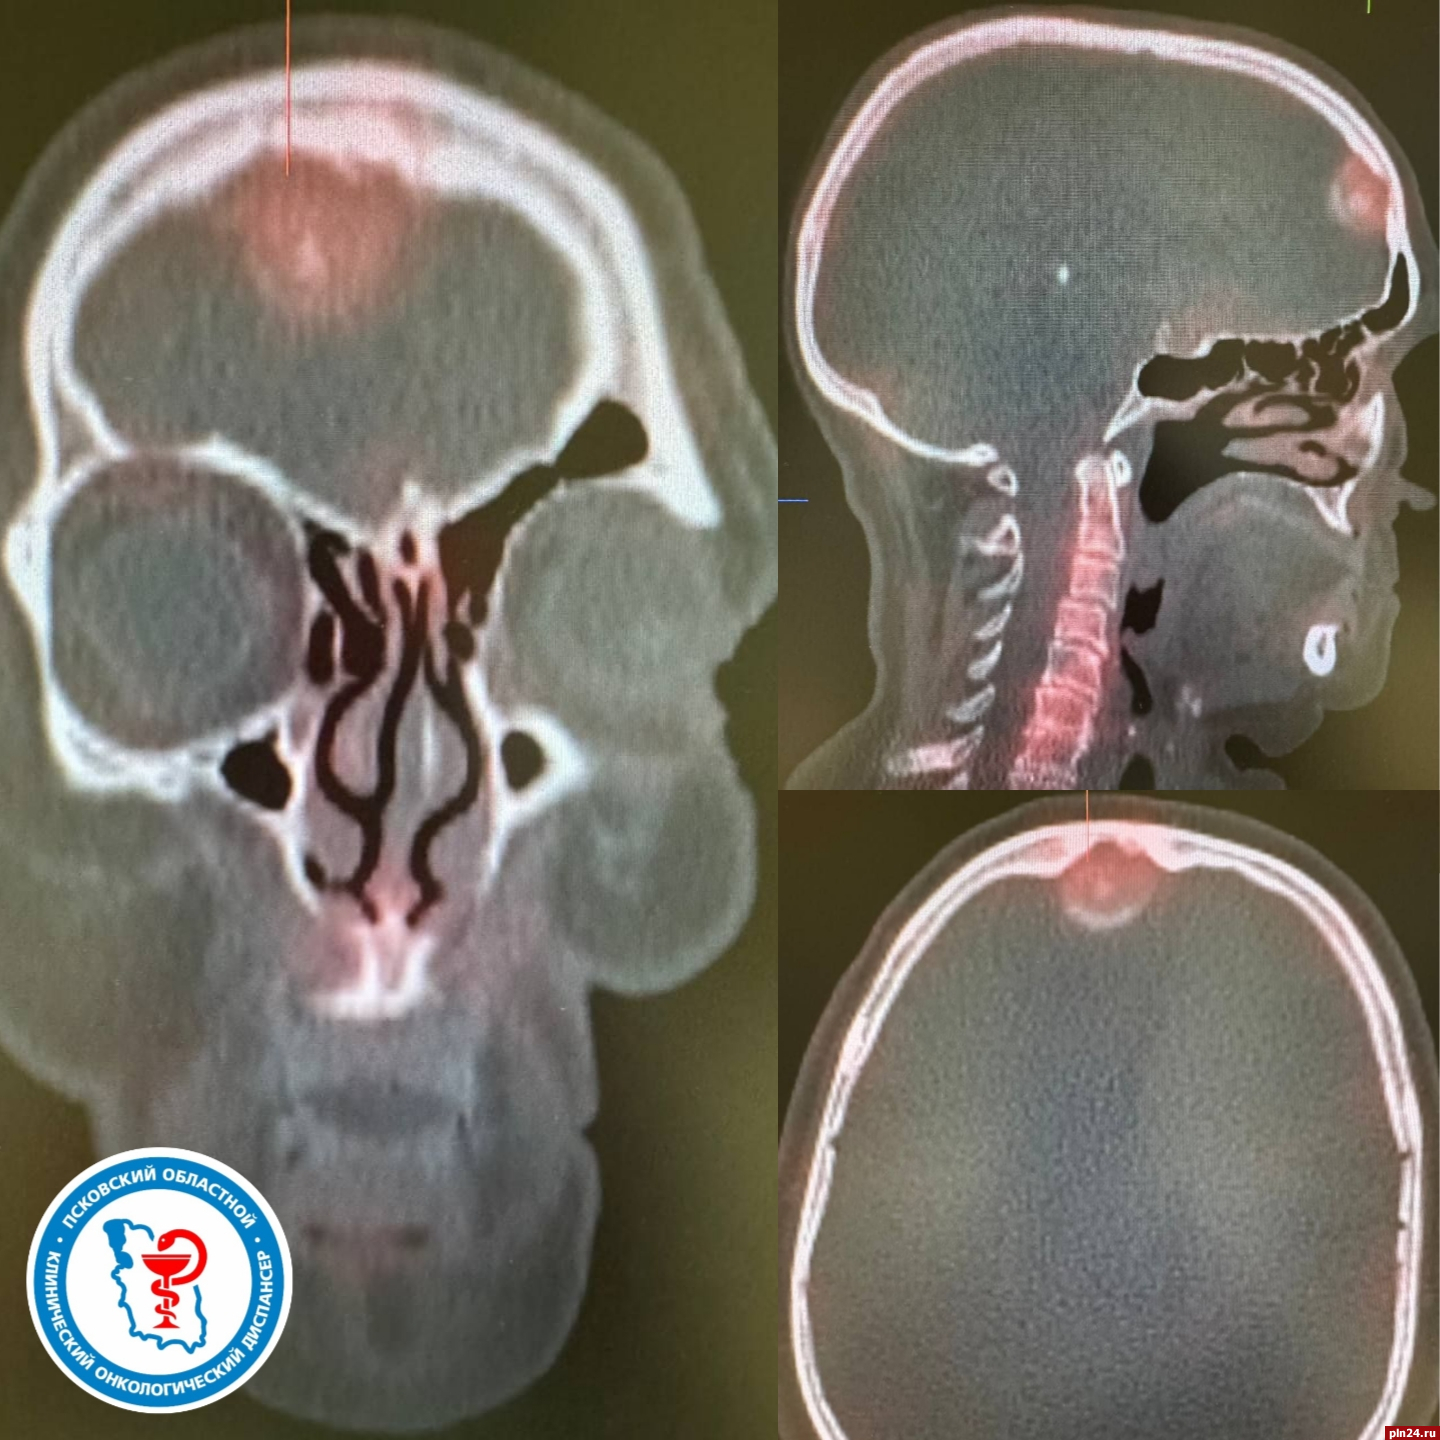

Затем пациентке провели ОФЭКТ-КТ (метод медицинской диагностики, сочетающий в себе однофотонную эмиссионную компьютерную томографию (ОФЭКТ) и рентгеновскую компьютерную томографию (КТ) - прим. ред.), в ходе которого в лобной области головного мозга было выявлено новообразование, которое плотно прилегало к лобной кости.

Для более детального изучения новообразования ей рекомендовали провести магнитно-резонансную томографию головного мозга с внутривенным контрастированием. Более четкие изображения при данном исследовании позволили дифференцировать новообразование от метастатического поражения и помогли врачу выявить менингиому. Выявление опухоли стало важным этапом в диагностическом процессе, так как это новообразование могло оказывать давление на окружающие ткани и вызывать описанные пациенткой симптомы.